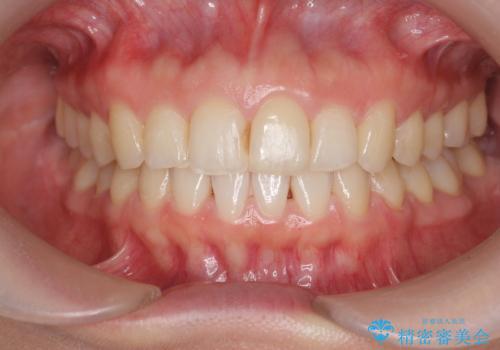

[マウスピース矯正] がたがたの歯並びをきれいにしたい

![[マウスピース矯正] がたがたの歯並びをきれいにしたいの症例 治療前](https://seimitsushinbi.jp/wp/wp-content/uploads/2025/06/0d238550c8a0fddc4de7b2c337c6c786-500x350.jpg?v=1750323380)

![[マウスピース矯正] がたがたの歯並びをきれいにしたいの症例 治療後](https://seimitsushinbi.jp/wp/wp-content/uploads/2025/06/IMG_0002-2-500x350.jpg?v=1750323305)